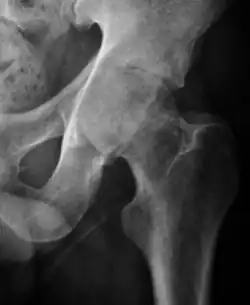

Plain radiography allows us to categorize the hip as normal or dysplastic or with impingement signs (pincer, cam, or a combination of both). Besides these, pathologic processes like osteoarthritis, inflammatory diseases, infection, or tumors can also be identified (Figure 1).[1]

Figure 1.

-

Radiography in normal hip -

X-ray in pincer impingement type of hip dysplasia -

X-ray of cam -

Hip in osteoarthritis -

Septic arthritis

- Osteoarthritis

In adults, one of the main indications for radiographs is the detection of osteoarthritic changes (Figure 1(e)). Nevertheless, radiographs usually detect advanced osteoarthritis that can be graded according to the Tönnis classifications. The grading system ranges from 0 to 3, where 0 shows no sign of osteoarthritis. Intermediate grade 1 shows mild sclerosis of the head and acetabulum, slight joint space narrowing, and marginal osteophyte lipping. Grade 2 presents with small cysts in the femoral head or acetabulum, moderate joint space narrowing, and moderate loss of sphericity of the femoral head. Grade 3 is the severest form of osteoarthritis, which manifests as severe narrowing of the joint space, large subchondral cyst with productive bone changes that may lead to deformity of the bone components of the joint, while secondary osteoarthritis due to calcium pyrophosphate deposition can be diagnosed when calcification of hyaline cartilage and fibrocartilage is detected.[1]